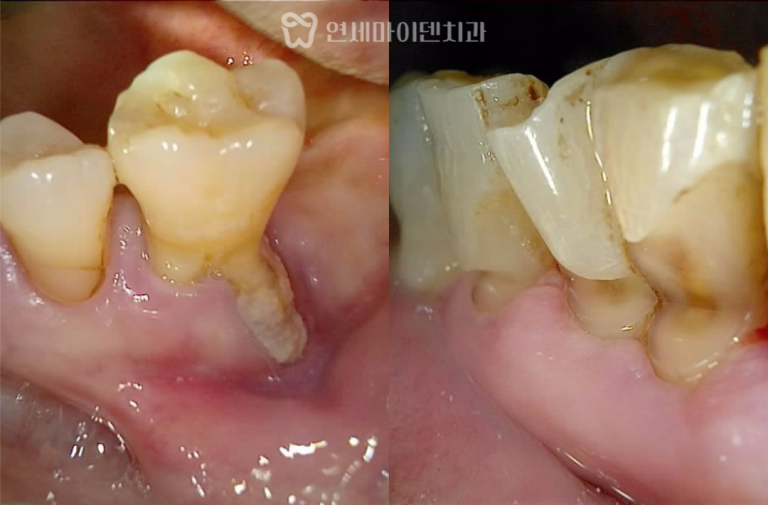

발치 즉시 임플란트 증례: 잇몸여드름, 치근파절

발치 즉시 임플란트 증례: 잇몸여드름, 치근파절 잇몸에서 고름이 반복적으로 올라오거나잇몸이 붓고 가라앉기를 반복하는 경우, 단순한 잇몸…